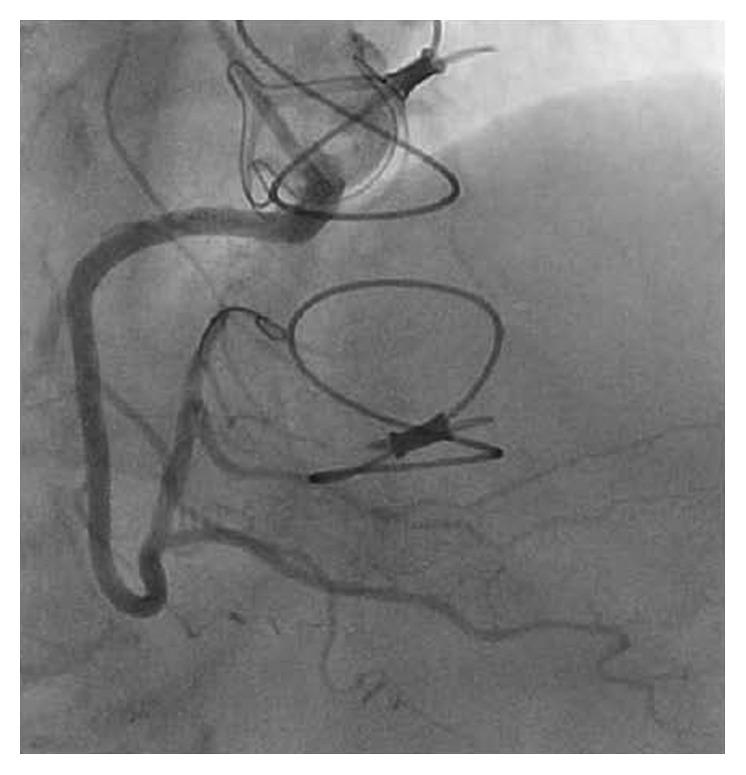

Coronary ostial stenosis is a rare but potentially life-threatening complication that occurs in 1%-5% of patients who undergo surgical aortic valve replacement (SAVR). Symptoms typically appear within the first 6 months and almost always within a year after SAVR. We report an unusually delayed presentation of non-ST segment elevation myocardial infarction due to coronary ostial stenosis 22 months after SAVR. A 71-year-old woman underwent uncomplicated SAVR with a bioprosthetic valve in August 2015 for severe aortic stenosis. A preoperative coronary angiogram demonstrated widely patent left and right coronary arteries. In June 2017, the patient presented to the hospital with chest pain. An electrocardiogram demonstrated 1 mm ST segment depression in the anterolateral leads, and serum troponin I level was elevated to 2.3 ng/ml. Diagnostic coronary angiography revealed severe ostial stenosis (99%) of the right coronary artery. A bare-metal stent was successfully placed with an excellent angiographic result, and the patient was asymptomatic at 4 months of follow-up after the procedure. As seen in our case, coronary ostial stenosis should be considered in the differential diagnosis of chest pain or arrhythmia in patients presenting with a history of SAVR, even if the procedure was performed more than 1 year prior to presentation.

冠状动脉开口狭窄是一种罕见但可能危及生命的并发症,发生在1%-5%接受外科主动脉瓣置换术(SAVR)的患者中。症状通常在术后前6个月内出现,几乎总是在SAVR术后一年内出现。我们报告了一例SAVR术后22个月因冠状动脉开口狭窄导致的非ST段抬高型心肌梗死的异常延迟表现。一名71岁女性于2015年8月因严重主动脉瓣狭窄接受了生物瓣膜置换的SAVR手术,手术过程顺利。术前冠状动脉造影显示左、右冠状动脉广泛通畅。2017年6月,该患者因胸痛入院。心电图显示前侧壁导联ST段压低1mm,血清肌钙蛋白I水平升高至2.3ng/ml。诊断性冠状动脉造影显示右冠状动脉严重开口狭窄(99%)。成功置入裸金属支架,血管造影结果良好,术后4个月随访时患者无症状。正如我们病例中所见,对于有SAVR病史的胸痛或心律失常患者,即使手术在出现症状前1年以上进行,在鉴别诊断时也应考虑冠状动脉开口狭窄。